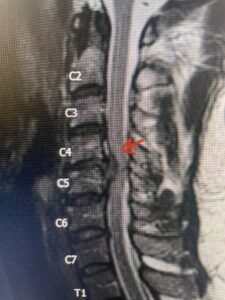

Fig 2a Sagittal and axial T2 weighted cervical MRIs demonstrating large C4 5 herniated disc with spinal cord compression red arrows

Fig. 2a Sagittal T2-weighted cervical MRI demonstrating large C4-5 herniated disc with spinal cord compression (red arrow)

Fig: 2b Axial T2-weighted cervical MRI demonstrating spinal cord compression from C4-5 herniated disc (red arrow)

This 47-year-old male who four months prior was lifting weights developed sharp pain in his neck. After that he developed progressive numbness in his arms, neck pain and headache. He said that the right arm was worse than the left. On examination the patient had long tract weakness on the right side which included his triceps, finger extensors, hip flexors, and dorsiflexors. The patient did not have hyperreflexia. MRI (Fig. 2) demonstrated a massive, extruded disc herniation with severe cord compression. The patient because of progressive myelopathy and spinal cord compression was indicated for anterior cervical discectomy and fusion at C4-5 (Fig. 3). Patient had significant improvement of weakness and numbness post operatively.